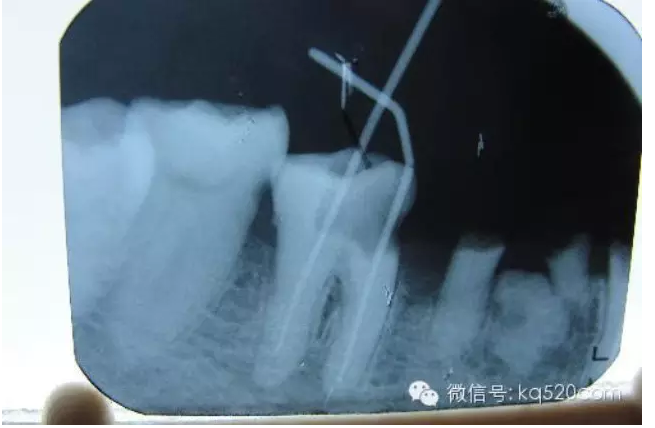

前面我們講過,牙齒內(nèi)部實際上是一個空腔,這個空腔我們稱之為“根管系統(tǒng)”。同單純的“爛神經(jīng)”相比,“根管治療”不僅僅是要將“根管”中的牙髓“殺死”,還要將牙髓從“根管”中清除出來,然后要進行徹底清理和嚴格消毒,并用人工的充填材料將“根管”嚴密填塞。這就是所謂的“根管治療”。一個“根管治療”做得是否完善,會在很大程度上決定了這顆牙齒的壽命。而且,不僅僅是對于牙髓炎,牙齒的其他疾病(如根尖周炎等)也需要采用根管治療的方法才能得到治愈。從傳統(tǒng)的根管治療三部曲(即根管預備、根管消毒和根管充填)來講,一般的根管治療需要三次。但是這僅僅是理論上的情況,實際上因患者而異,因牙而異,因醫(yī)生的技術水平而異?,F(xiàn)代根管治療技術有了飛躍性的發(fā)展,有些根管治療甚至可以一次完成。